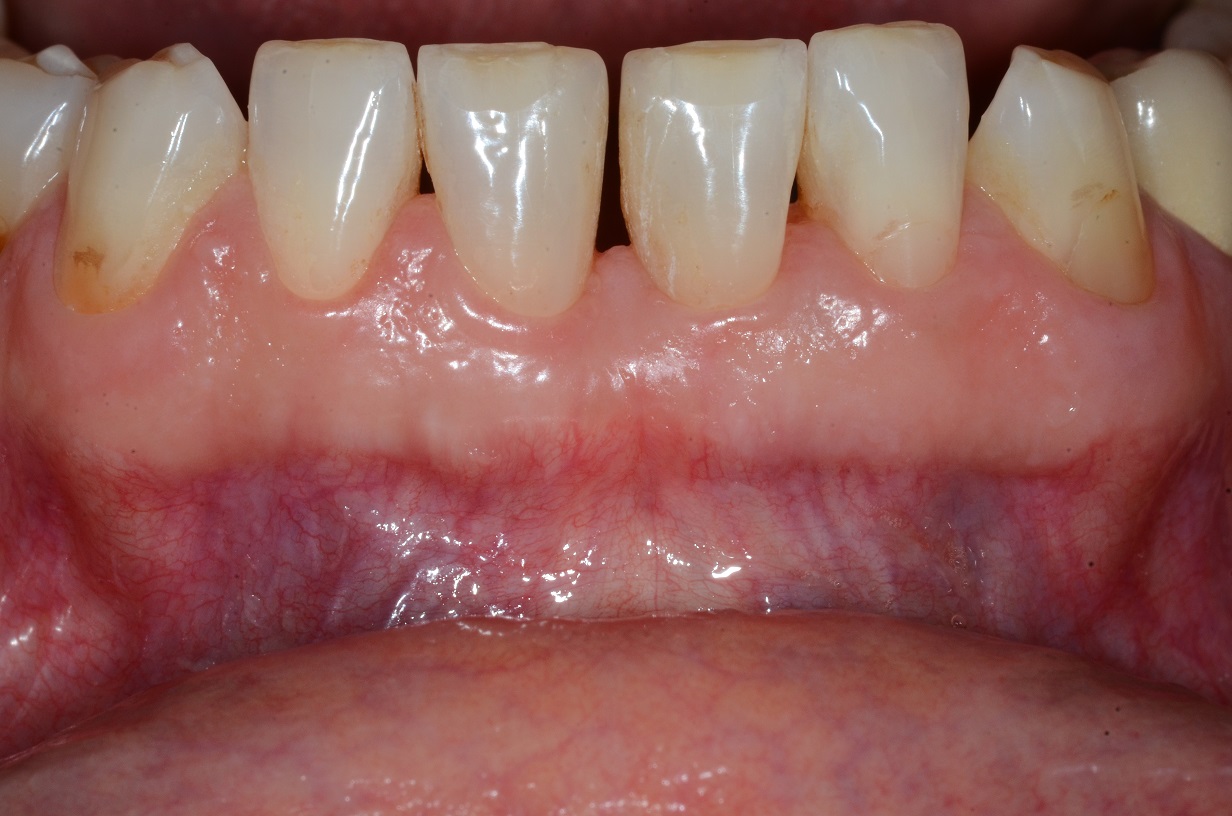

02/13 - Baseline radiograph.

Wide intrabony defect treated with the modified papilla preservation flap in conjunction with Straumann® Emdogain® and autogenous bone - Dr. B. Molnar